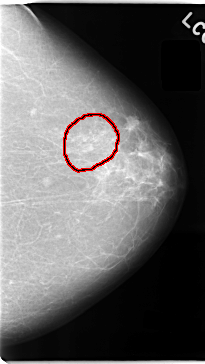

FILE: C_0040_1.LEFT_CC.OVERLAY

TOTAL_ABNORMALITIES 1

ABNORMALITY 1

LESION_TYPE MASS SHAPE IRREGULAR MARGINS SPICULATED

ASSESSMENT 5

SUBTLETY 5

PATHOLOGY MALIGNANT

TOTAL_OUTLINES 1

BOUNDARY